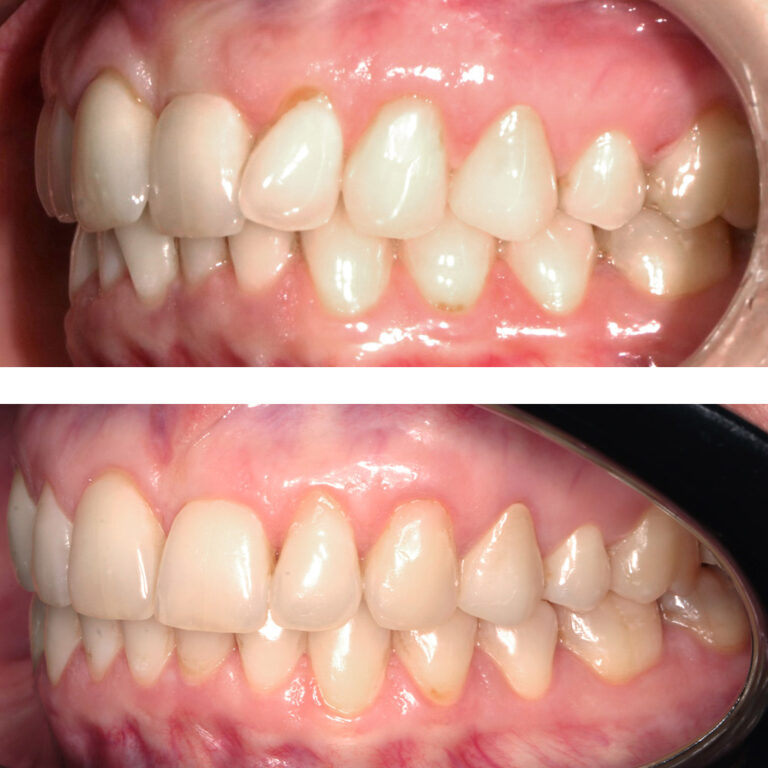

Кейс 21

Количество кап ВЧ 32

Количество кап НЧ 32

ДО

ПОСЛЕ